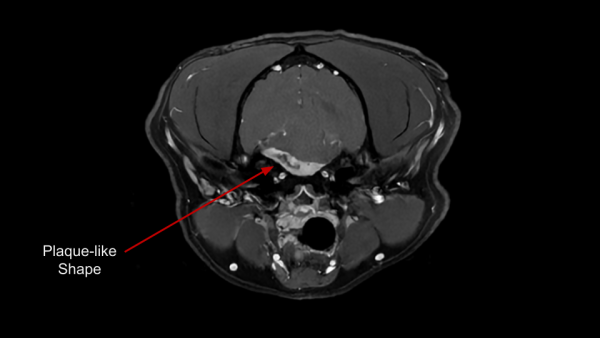

Meningiomas are typically benign and slow growing tumors arising from the meninges. They are commonly well encapsulated, focal, round, and solid. Less commonly, meningiomas can be invasive, have plaque-like shapes, or varied internal composition. They can occur anywhere along the CNS, but are most common around the brain. Meningiomas have a few key identifying characteristics; some or all may be present:

- Vivid contrast enhancement

- 'Dural Tail' sign